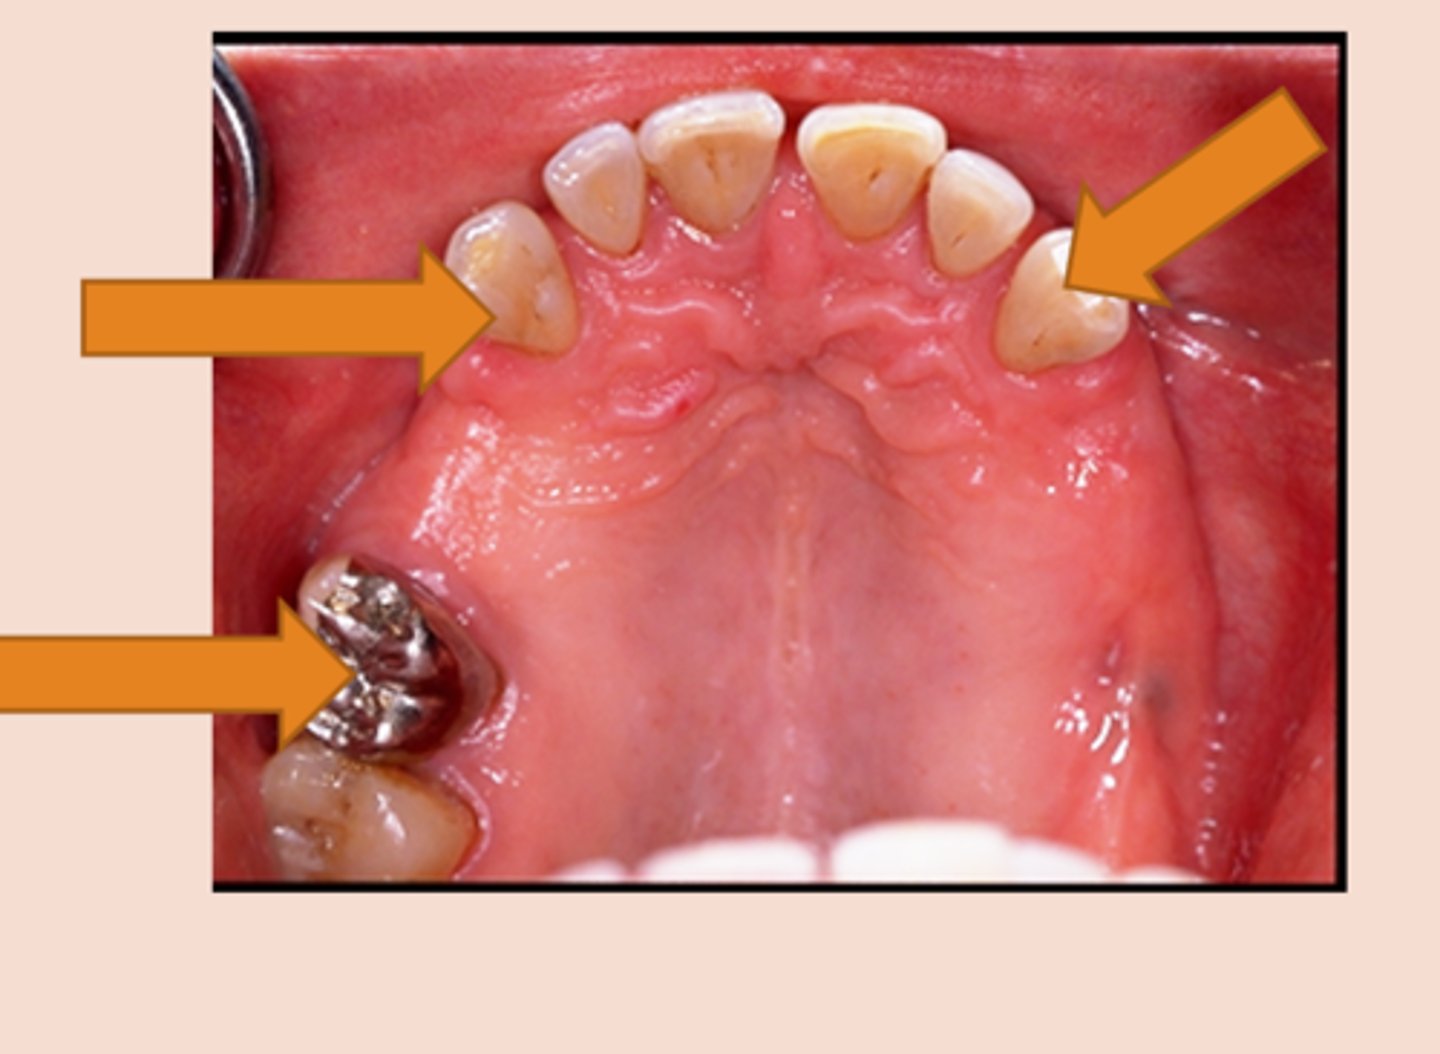

Guide planes

Are prepared (occasionally natural) axial surfaces of teeth against which the RPD glides during insertion and removal - defines the path of insertion

parallel

Guide planes must be ______ to each other and to the path of insertion

occlusal

Guide planes are Located in the _____ portion of the tooth (a proximal or lingual plate refers to the part of the RPD framework that is in contact with the guide plane)

natural curvature of the tooth buccolingually

Whether adjacent to tooth-borne or extension base segments, the prepared surface for RPD should not be a straight “slice” buccolingually, but should follow the ....